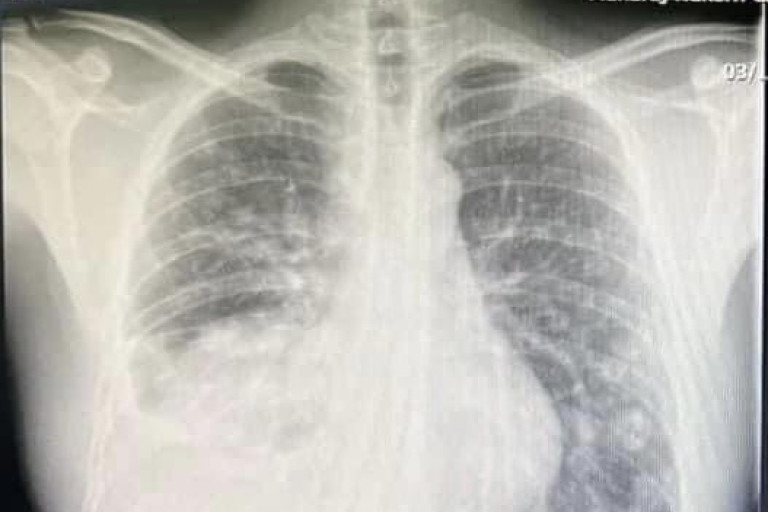

เพราะหมอหนุ่มที่ออกกำลังสม่ำเสมอ เล่นกีฬา กินคลีน ไม่สูบบุหรี่ ดื่มน้อยมาก ทำงานไม่เครียด นอน เป็นเวลา

กลับตรวจเจอมะเร็งปอดระยะลุกลาม ปอดขวาหายไปครึ่งนึงแล้ว